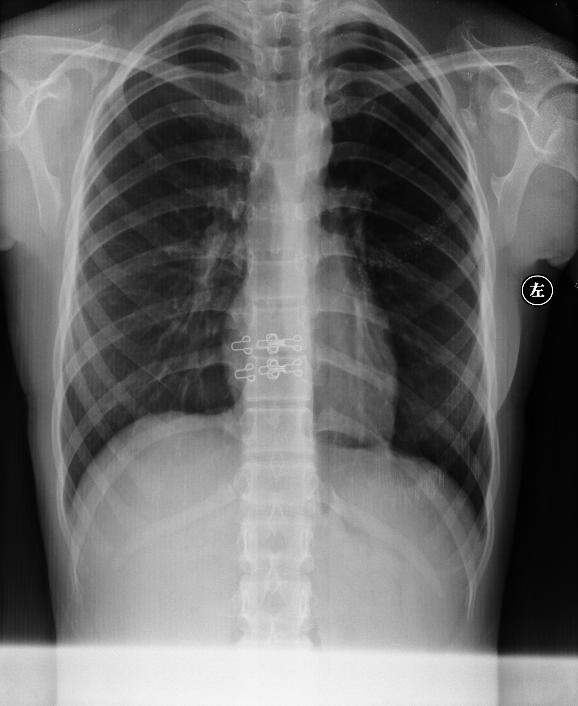

CL2917:肩胛骨多发骨软骨瘤.

女,16岁.

肩胛骨多发骨软骨瘤